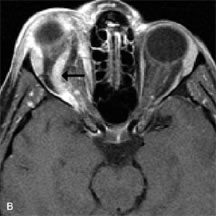

MRI is an excellent modality for demonstrating enlargement of the cavernous sinus and dilation of the superior ophthalmic vein in patients with high-flow carotid-cavernous fistulas (Fig. 14).37MRA may be helpful in the evaluation of the venous outflow pattern. The rapidly flowing blood in these vascular structures carries the excited protons out of the section before they can be imaged, resulting in their dark appearance.5 In low-flow dural arteriovenous malformations, MRA may help define the arterial feeding vessels.45

Fig. 14. Patient with Ehlers-Danlos syndrome who presented with abrupt onset of severe proptosis. A-C. Postcontrast fat-suppressed T1-weighted MR scans demonstrate marked proptosis and engorgement of the extraocular muscles and superior ophthalmic vein (arrows). D. T2-weighted scan through the cavernous sinus demonstrates enlargement and arterialized flow void within the right cavernous sinus (open arrow).